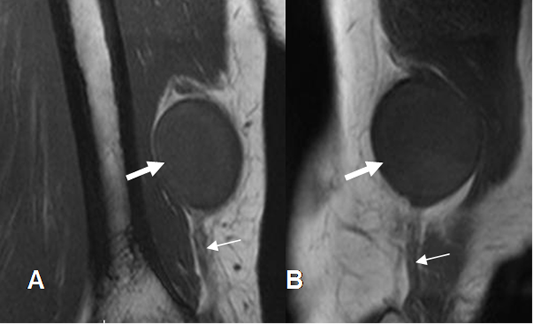

Fig 54 B. Neurofibroma del ulnar.

A: RM coronal y B: RM sagital en T1. Imagen ovalada y sólida (Flecha gruesa), en relación con el nervio ulnar. (Flecha delgada.)